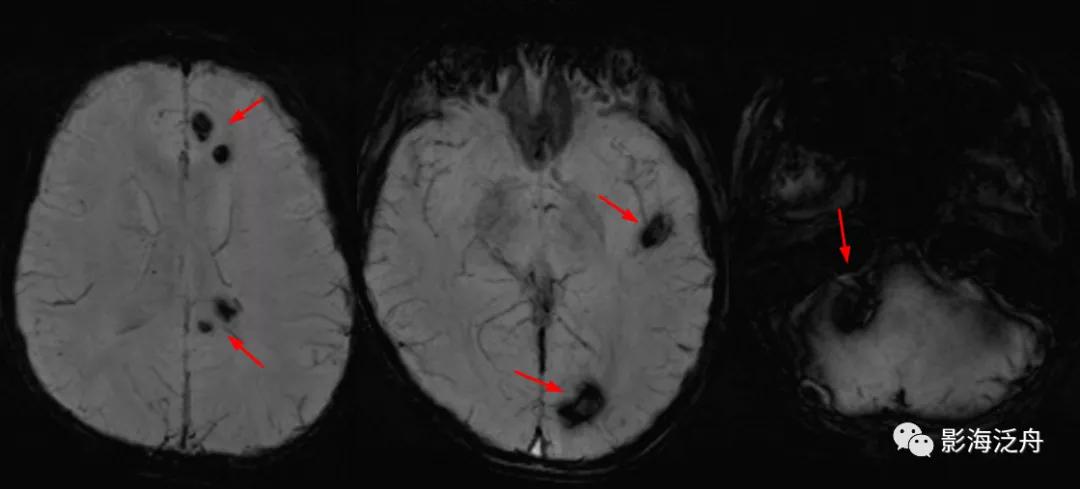

话不多说,上病例:患者女,12岁,头晕、头痛伴呕吐一天,无发热,无咳嗽,入院后行MR平扫检查,如下图↓↓

上图可见右侧桥臂一类圆形异常信号,T1WI呈中央稍低信号,边缘环形高信号,T2WI以低信号为主,局部可见液液分层(红箭),高、低b值DWI显示病变区域信号丢失。通过上述信号改变,不难看出是一个急性期血肿(血肿分期详见 MR上脑出血信号的演变机制)。

比如本例患者就没有及时进一步检查,只是保守治疗后常规复查,直到一年以后才做了SWI,如下图。

SWI可见左侧大脑半球多发低信号结节(红箭),病灶多位于皮髓质交界区,直径较为一致,结合患者年龄、病史,不难诊断这是一例多发海绵状血管瘤。